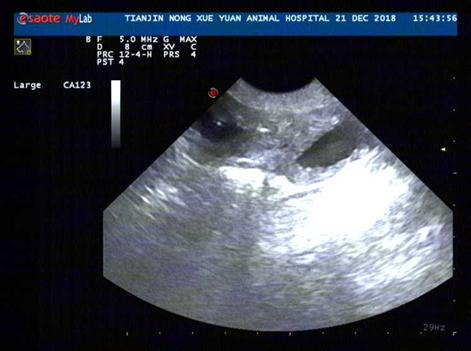

超声诊断结果

诊断:X光见膀胱结石,前列腺肿大,B超见前列腺肿大,伴有轻微囊肿